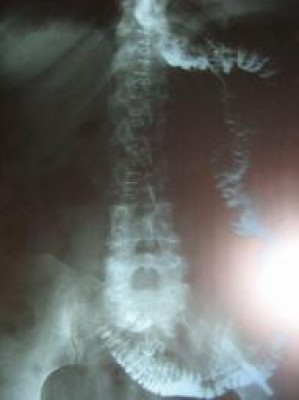

Post Image

Cáncer gástrico entre cuerpo y fondo gástrico